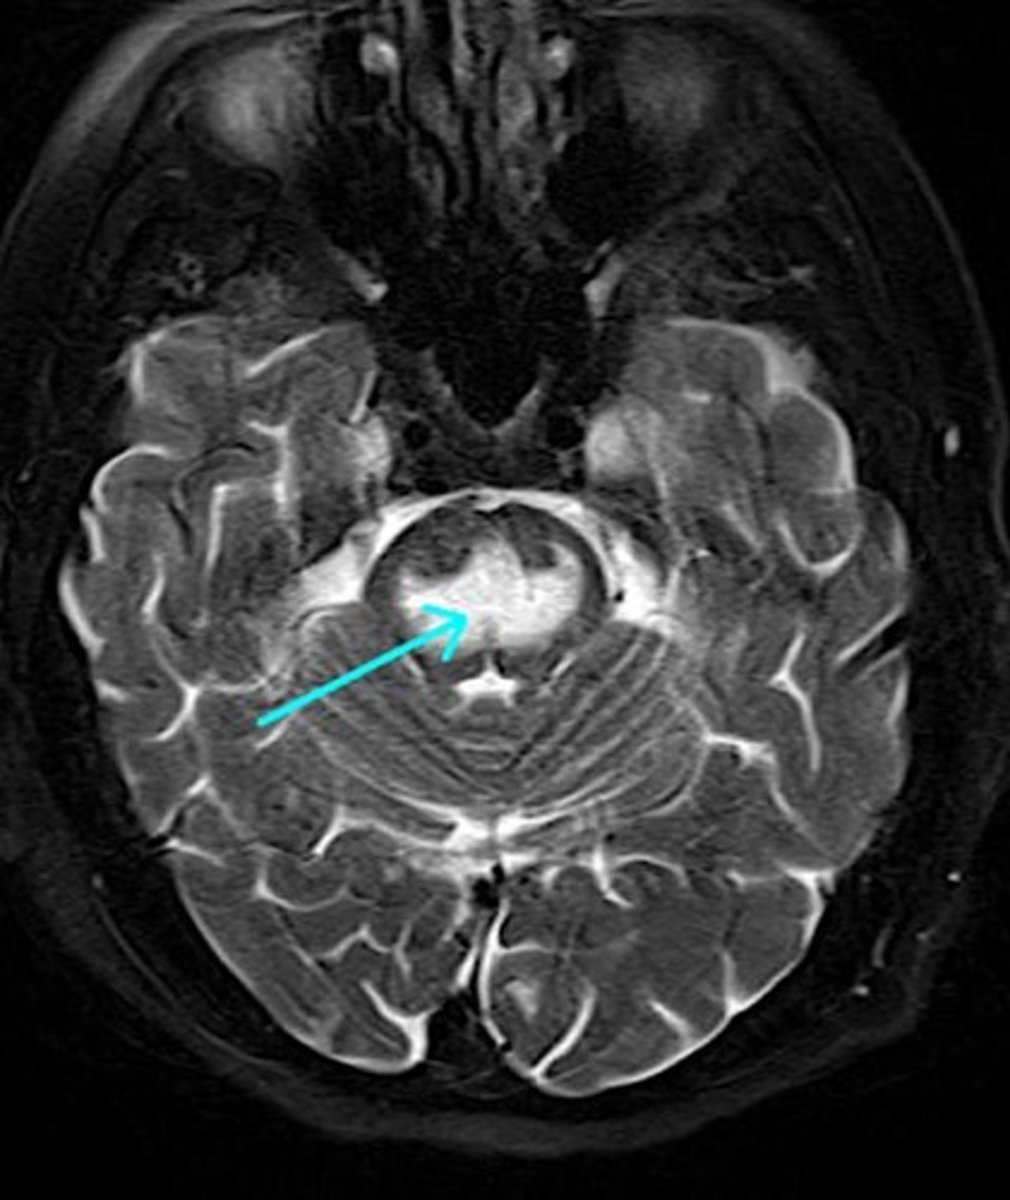

MRI findings in diffuse axonal injury

USMLE can show MRI showing scattered hyperintense (white) lesions.